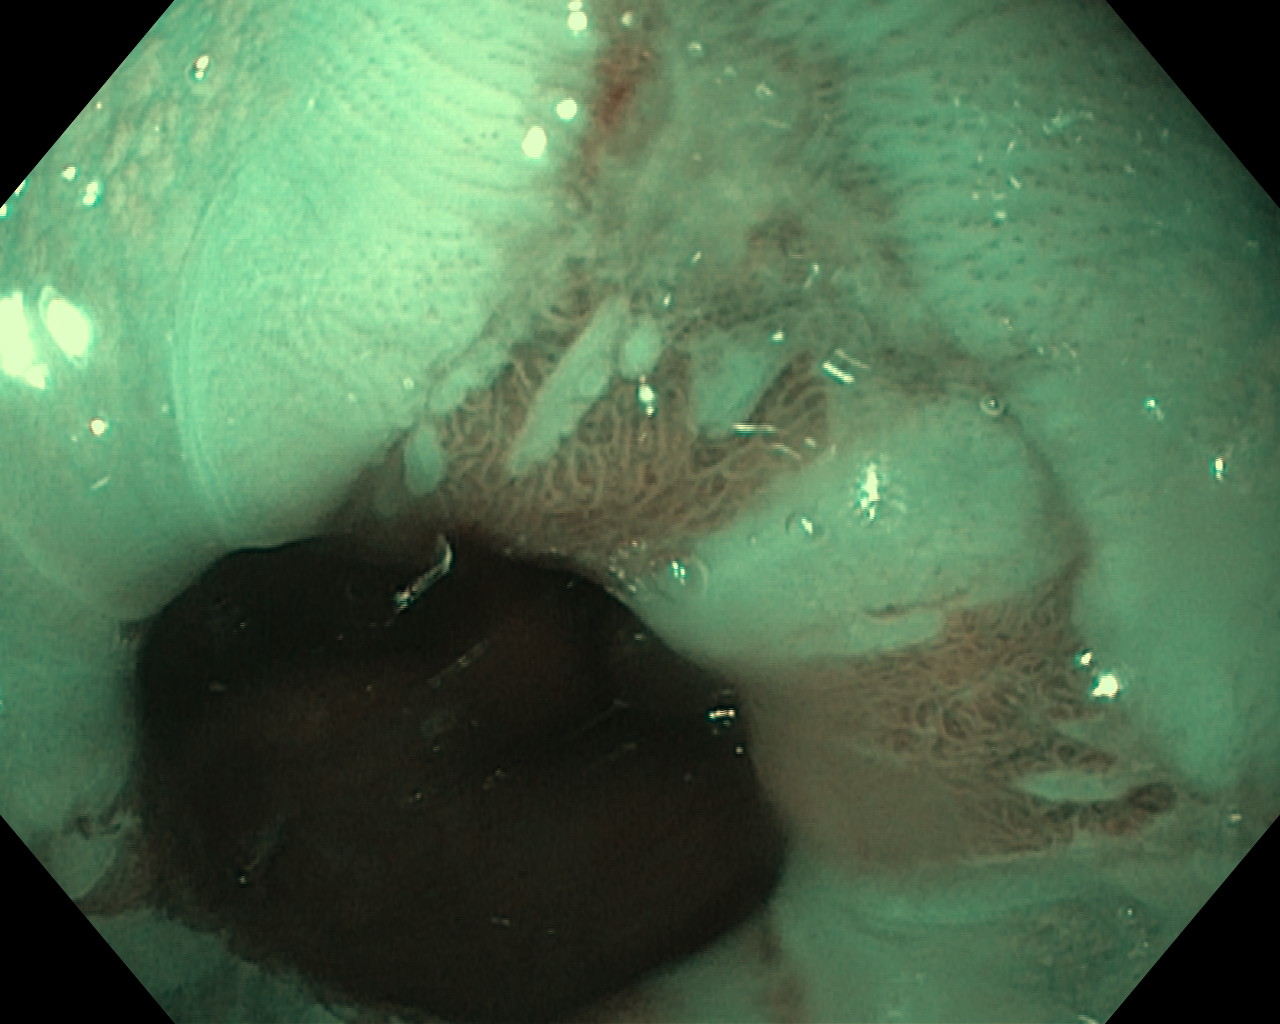

Przełyk Barretta